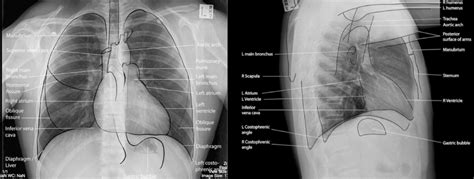

- RTG (röntgenové) vyšetrenie hrudníka: Základná metóda na zobrazenie pľúc a odhalenie zápalu pľúc, pleurálneho výpotku alebo iných abnormalít.

Posúdenie začína anamnézou. Lekár určí priebeh infekcie, ako dlho trvala horúčka, či sa vyskytol zápal pľúc, či sú prítomné chronické ochorenia pľúc alebo srdca a ako sa v priebehu času menila dýchavičnosť. Rýchlosť nástupu príznakov je jedným z najinformatívnejších ukazovateľov. Ďalej sa merajú vitálne funkcie: frekvencia dýchania, pulz, krvný tlak, teplota a SpO2. Aj keď sa pacient „cíti normálne“, tieto parametre môžu odhaliť skrytú závažnosť stavu. Prvým inštrumentálnym vyšetrením pri pretrvávajúcej dýchavičnosti je röntgen hrudníka. Pomáha identifikovať zápal pľúc, pleurálny výpotok a príznaky preťaženia srdca. Ak sú údaje nepresvedčivé a príznaky sú závažné, použije sa CT vyšetrenie. Ak sú snímky pľúc normálne, vykoná sa funkčné vyšetrenie dýchania vrátane spirometrie a difúznych testov. To umožňuje odhaliť bronchiálnu obštrukciu alebo zníženú difúziu, čo je typické pre postinfekčné zmeny. Ak existuje podozrenie na srdcovú príčinu, vykoná sa elektrokardiogram a echokardiografia a niekedy sa merajú natriuretické peptidy. Ak existuje riziko pľúcnej embólie, vyšetrí sa D-dimér a v prípade potreby sa vykoná pľúcna angiografia.